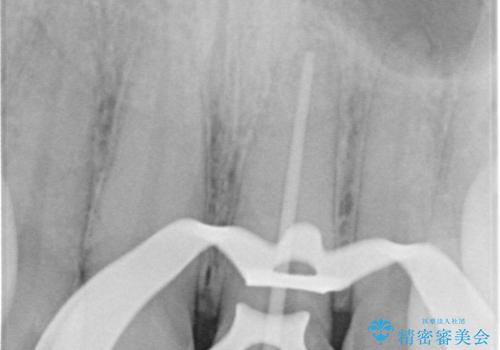

精密根管治療では、菌を入れない環境を作り見逃しが無いようにマイクロスコープを使って治療する事が大切です。

まだ誰も触っていない根管ならばほとんどのケースで治せる事が出来ます。